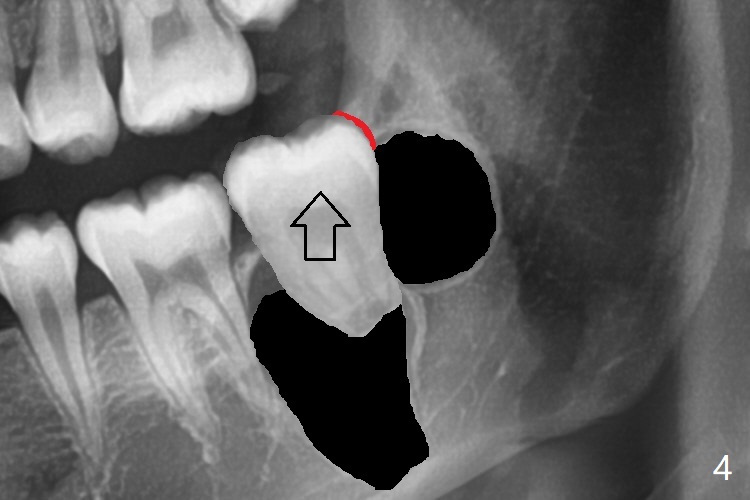

Treatment planning of surgical access to the impacted 7 (Fig.1) before CT analysis (to be canceled due to finance) include extraction of 8 (Fig.2) and removal of the bone coronal to 8 (Fig.3 red) so that there will be no bony block to 7 eruption (Fig.4). Place PRF or collagen plug in 8 socket to facilitate healing (Fig.3). Attach a retraction chain to the occlusal or buccal surface of 7 (Fig.6 pink) whenever it is convenient in term of hemorrhage and access (as mesial as possible). Remove 16 niti wires for brushing when the patient arrives. Cut 18 ss wire longer in the LL end (Fig.6 green to be bent to hook power chain (yellow)). Incision is shown as red in Fig.5. After 3 month delay, the thick buccal plate is removed from LL8 (1st) and 7 (2nd in sequence, as compared to Fig.2) to expose these unerupted teeth. In fact CT is not taken to decrease budget on the divorcing parents. A retraction chain is placed before extraction of LL8 with an intention to reduce hemorrhage (Fig.7). Although extraction requires several sectioning of the tooth, hemorrhage is mild to moderate. Instead of PRF and sticky bone (as compared to Fig.3), Osteogen plug is placed in the socket (Fig.8 OP). The bony septum between the 2 sockets is intentionally kept in place (*). 事实的确这样发生(图九:*)。埋伏牙不仅上移(^),而且远中移动(>),因为牵引方向(红虚线(橡皮筋),挂在上牙弓丝(图九:20ss:图十:18ss(之前))远端勾,积极牵引三个星期)。下次左上7放置舌侧纽扣,让病人更换橡皮筋。其实纽扣粘不住,上牙弓丝远中勾也不现实,只能使用橡皮筋挂在左上6,经常断。术后6个月,左下7继续上移(图十一)。这种低效率牵引仍然有效,牙齿继续上移,牙根长长(图十二:空箭头),但是受到左下6远中阻挡(*),所以下次在左上7咬合面装置舌侧纽扣和closed spring,改善牵拉方向(红箭头)。